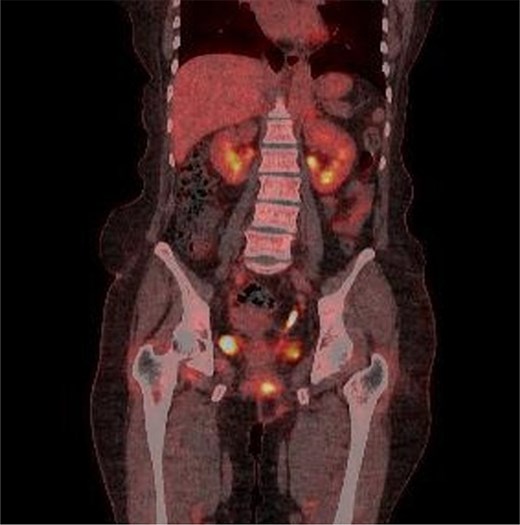

A 59-year-old female patient was referred to our hospital with severe left buttock pain lasting 5 days. Although she had no co-morbidities, she was previously diagnosed with hemorrhoids at the local clinic due to perianal pain persisting for 1 month. The patient had no medical or surgical history. Her initial body temperature was 38.4°C, blood pressure was 110/60 mmHg, heart rate was 98 beats/min, and her oxygen saturation was 98% on room air. On physical examination, erythema and hardness were noted in the left perineum and buttock areas. Additionally, dilated piles were observed on anus (Fig. 1). Given the clinical suspicion of FG, a computed tomography (CT) scan and blood tests were urgently performed. The CT scan demonstrated abscess formation along with severe emphysema in the left perineum and buttock (Fig. 2A). Blood tests showed leukocytosis of 41 840/μl with neutrophil left shift and an elevated C-reactive protein level of 33.4 ng/dl. The patient was finally diagnosed with FG, indicated by a severity index score of 6 points [6]. After initiating fluid resuscitation and broad-spectrum antibiotics, extensive debridement of the perineum was executed (Fig. 2B). However, due to clinical deterioration after general anesthesia, staged debridement was performed, and the patient was admitted to the intensive care unit for stabilization. Subsequent debridement and a diverting colostomy were performed 3 days after surgery. After 1 week in intensive care, the patient was transferred to the general ward where additional wound debridement and revisions were conducted. Two months after initial surgery, the surgical wound had completely healed, and wound closure was performed. Although inflammation had subsided, indurated tissue persisted around the anus, which had become so constricted that a digital rectal examination was impeded. Therefore, a biopsy of the perianal tissue was taken. Histopathological examination identified moderately differentiated squamous cell carcinoma, and HPV 16 was detected (Fig. 3). Pelvic magnetic resonance imaging (MRI) revealed anorectal cancer with invasion into both levator muscles and indeterminate lymph nodes in the bilateral external iliac, right obturator, and bilateral inguinal chains (Fig. 4). Positron emission tomography demonstrated an intensely hypermetabolic mass extending from the anus to the rectum, accompanied by multiple hypermetabolic lymph nodes in the left common iliac, left external iliac, right internal iliac, and bilateral inguinal regions (Fig. 5). Consequently, concurrent chemoradiotherapy (CCRT) employing mitomycin and 5-fluorouracil was initiated. The patient received a total radiation dose of 63 Gy in 35 fractions over 8 weeks. Elective nodal irradiation included the bilateral inguinal, internal iliac, and mesorectal nodal basins, in accordance with standard guidelines. Although follow-up MRI after CCRT showed a significant reduction in the size of the primary tumor and lymph nodes, we decided to perform a radical resection (Fig. 6). Robotic abdominoperineal resection was performed 3 months after CCRT, during which lateral pelvic lymph node dissection wasn’t conducted, as post CCRT imaging showed indeterminate lymph nodes suggestive of remission. Histopathological examination of the specimen revealed no residual tumor (ypT0N0). Although a minor surgical site infection occurred at the perineal wound, it was successfully treated with oral antibiotics and dressings at an outpatient setting. At 10 months post-surgery, the patient reported left pelvic pain, and follow-up imaging revealed suspected metastases in the left psoas, para-aortic area, supraclavicular node, right 10th rib, and lung. Consequently, the patient was scheduled for palliative chemotherapy.

Marked reduction in the size of the tumor and lymph nodes following CCRT.